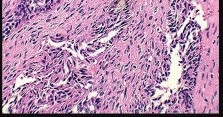

Question 3:

A 15-year-old boy presents with a permeative lytic lesion in the femoral diaphysis with aggressive periosteal reaction ('onion skinning'). Biopsy reveals uniform small round blue cells. Cytogenetic analysis of this tumor will most likely demonstrate which of the following translocations?

Correct Answer: t(11;22)

Explanation:

The clinical and radiographic description is classic for Ewing sarcoma. The characteristic cytogenetic abnormality is a balanced translocation t(11;22)(q24;q12), which fuses the EWS gene on chromosome 22 with the FLI1 gene on chromosome 11. This is seen in approximately 85-90% of Ewing sarcomas. t(9;22) is the Philadelphia chromosome (CML), t(X;18) is seen in synovial sarcoma, t(2;13) in alveolar rhabdomyosarcoma, and t(12;16) in myxoid liposarcoma.